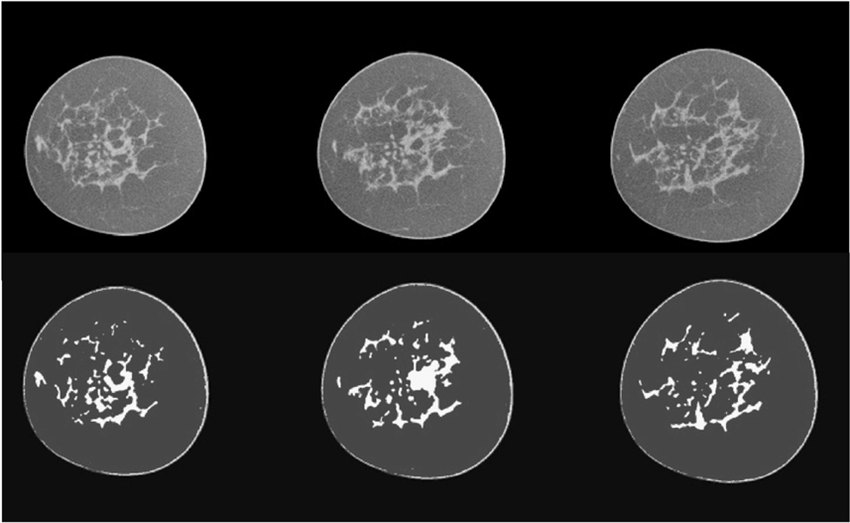

1. AI-Enhanced CT Image Denoising

Koning needed a way to lower radiation dose without compromising diagnostic clarity which is a key requirement for patient safety and clinical accuracy. CtrlCV delivered an advanced AI denoising engine that preserves fine breast anatomy while removing noise, enabling images captured at 300 projections (low dose) to achieve clarity comparable to a 1500-projection reconstruction —up to three times clearer without increasing radiation. Unlike traditional smoothing techniques, our AI distinguishes true anatomy from noise, producing sharper, more reliable scans. This directly results in higher diagnostic confidence, improved patient safety, and a substantial upgrade in image quality across Koning’s 3D Breast CT system.